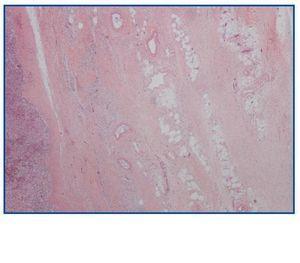

La necropsia demostró un proceso fibrosante sistémico (Figuras 1-4), con afectación de pelvis menor, retroperitoneo, en coraza alrededor de riñones, glándulas suprarrenales y páncreas, abarcando espacio periesplénico y perihepático; y mediastínico, en coraza alrededor de pericardio, arco aórtico y grandes vasos; y paquipleuritis derecha con fibrosis calcificada. Se apreciaron también: pancreatitis crónica fibrosa asociada, atrofia testicular, fenómenos de enfermedad aterombólica, hipertrofia ventricular izdª, y hepatopatía fibrosa crónica, en el contexto de un paciente con arteriosclerosis generalizada severa, con repercusión renal -nefroangiosclerosis bilateral con atrofia renal derecha, encefálica –infarto antiguo quístico izquierdo a nivel de ínsula-, y de colon –colitis isquémica rectosigmoide.

Figura 2.